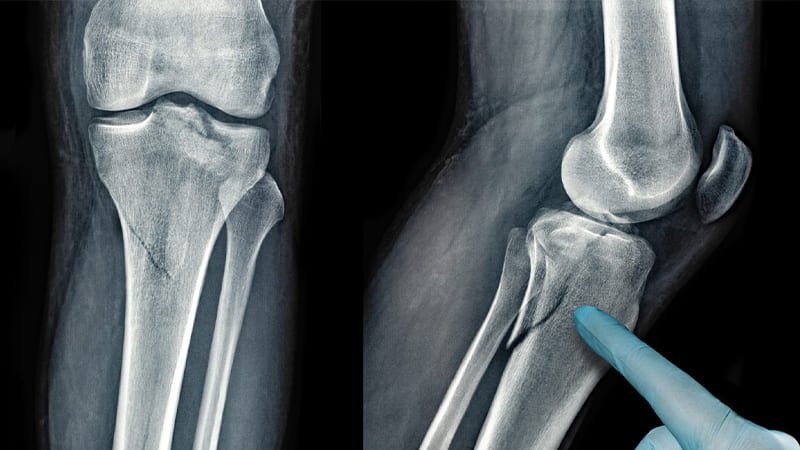

Serious wounds that may result in significant harm to bones, joints, and surrounding tissues are known as complex trauma and fractures.

A large accident or a catastrophic fall can result in numerous body parts being severely injured, a condition known as complex trauma. In order to address the short- and long-term complications, surgery and specialist care are typically necessary.

Often challenging to heal, complex fractures are intricate cracks in the bone. Broken bones, fractures that pierce through the skin and misaligned bones are a few possible examples. Surgery and cautious management to promote appropriate healing are typically required in the treatment of these fractures.

Complex fractures show specific traits, which could include:

- Soft tissue injury

- Serious damage to the cartilage

- Loss of bone as a result of severe trauma

- Numerous fractures present in a single bone

- Comminuted bone fragments

- Joint dislocation